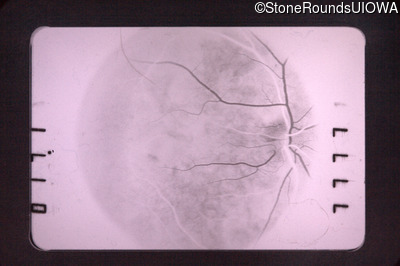

Visit at age: 47 years

Fluorescein Angiography - Left - 20/30 +1